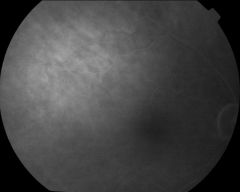

IM000025

IM000026

IM000027

IM000028

IM000029

IM000030